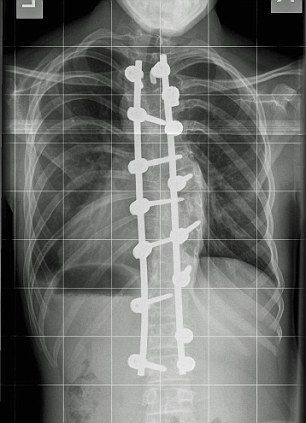

Ο Harvey Legge, έπασχε εκ γενετής από σοβαρή σκολίωση η οποία μάλιστα απειλούσε την λειτουργία των ζωτικών του οργάνων. Πρόσφατα λοιπόν υποβλήθηκε σε χειρουργείο σε εξειδικευμένη παιδιατρική κλινική όπου οι γιατροί σημείωσαν πως η κατάστασή του ήταν ιδιαίτερα σοβαρή γι' αυτό και έπρεπε να χειρουργηθεί. Και ευτυχώς που έγινε καθώς το παιδί απαλλάχθηκε από την κλήση 90 μοιρών που έκανε το πάνω μέρος του σώματός του με αφόρητους πόνους ενώ συγχρόνως, κάθε βράδυ ψηλώνει κατά περίπου δύο εκατοστά. Πλέον η κλήση της σπονδυλικής του στήλης έχει περιοριστεί στο 20% ενώ οι πόνοι έχουν υποχωρήσει αισθητά, με τον μικρό και τους γονείς του να δηλώνουν τρισευτυχισμένοι για τη συγκεκριμένη εξέλιξη.